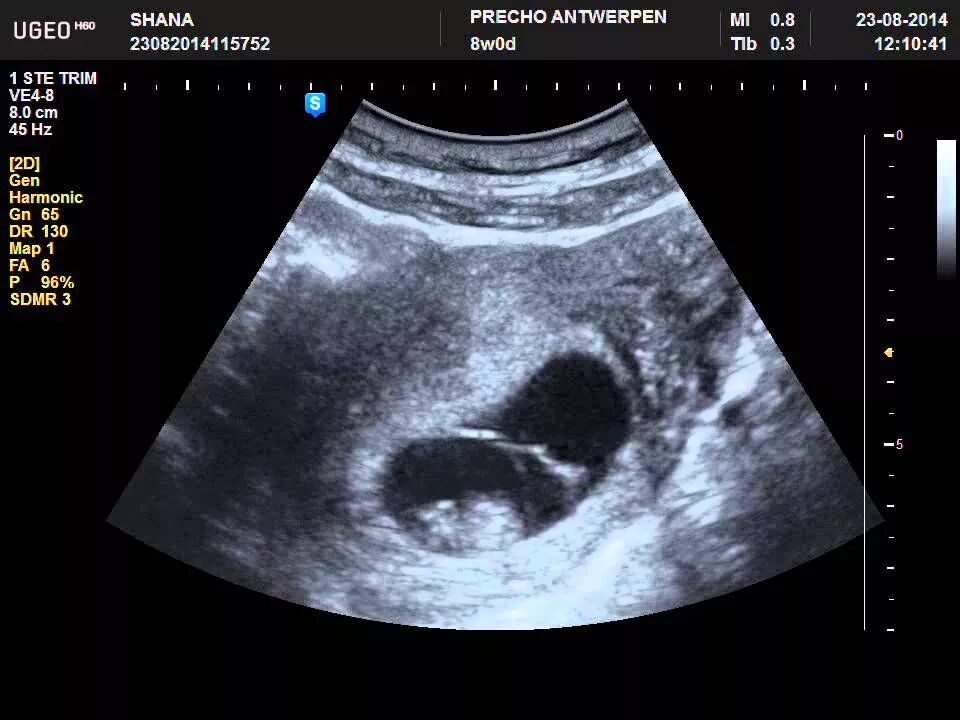

Как выглядит узи живота